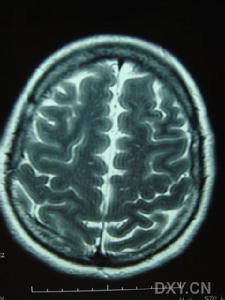

3.MRI是本病的重要診斷工具側腦室周圍及半卵圓中心可見均勻分布的點狀和結節狀T2WI高信號,基底核和腦橋也可見多數病人腦血管造影無異常,曾報告1例患者小動脈嚴重狹窄,另2例患者腦血管造影后神經體徵加重PET檢查僅1例嚴重基底核損傷的躁狂病人提示皮質代謝降低皮膚活檢是腦外部檢查的新手段,皮膚活檢發現嗜鋨顆粒樣物(GOM)沉積有重要診斷價值。可伴明顯抑鬱躁狂和自殺傾向,注意繼發的肺部感染尿路感染及褥瘡等。

影像學上有類似Binswanger病的表現,MRI顯示在腦室周圍白質、腦幹、小腦中腳、基底節區和丘腦部位多發性小的線狀、點狀病灶,可在皮質下對稱融合成片狀。CADASIL臨床確診標準:在可能CADASIL診斷標準的同時,與第19號常染色體連鎖和(或)病理證實有顆粒狀嗜鋨性物質沉積改變的小動脈病。可能為CADASIL的診斷標準:①50歲前發病;②出現下列臨床表現中至少2條:症狀持久的腦卒中發作、偏頭痛、明顯的情感異常、皮質下痴呆;③無腦血管病的危險因素;④常染色體顯性遺傳證據;⑤MRI顯示腦白質異常,而無腦皮質梗死灶。

⑥影像學檢查:MRI顯示非典型性腦白質病。可見,腦室周圍多發的梗死灶及白質變性,可累及兩側半球皮層、白質及腦室周圍、基底節、橋腦白質等部位。

影像學檢查示:患者姐弟的CT均可見,但當地的CT顯示欠清楚。患者的頭顱CT可見多發白質變性;MRI清晰可見多發白質變性及小梗死病灶,病灶大小不一,均呈長T1、長T2信號,病灶累及雙側半球、腦室周圍、腦幹、橋腦,小腦未見病灶;梗死灶分布在底節區,MRA(血管的磁共振影像)顯示顱內血管正常。